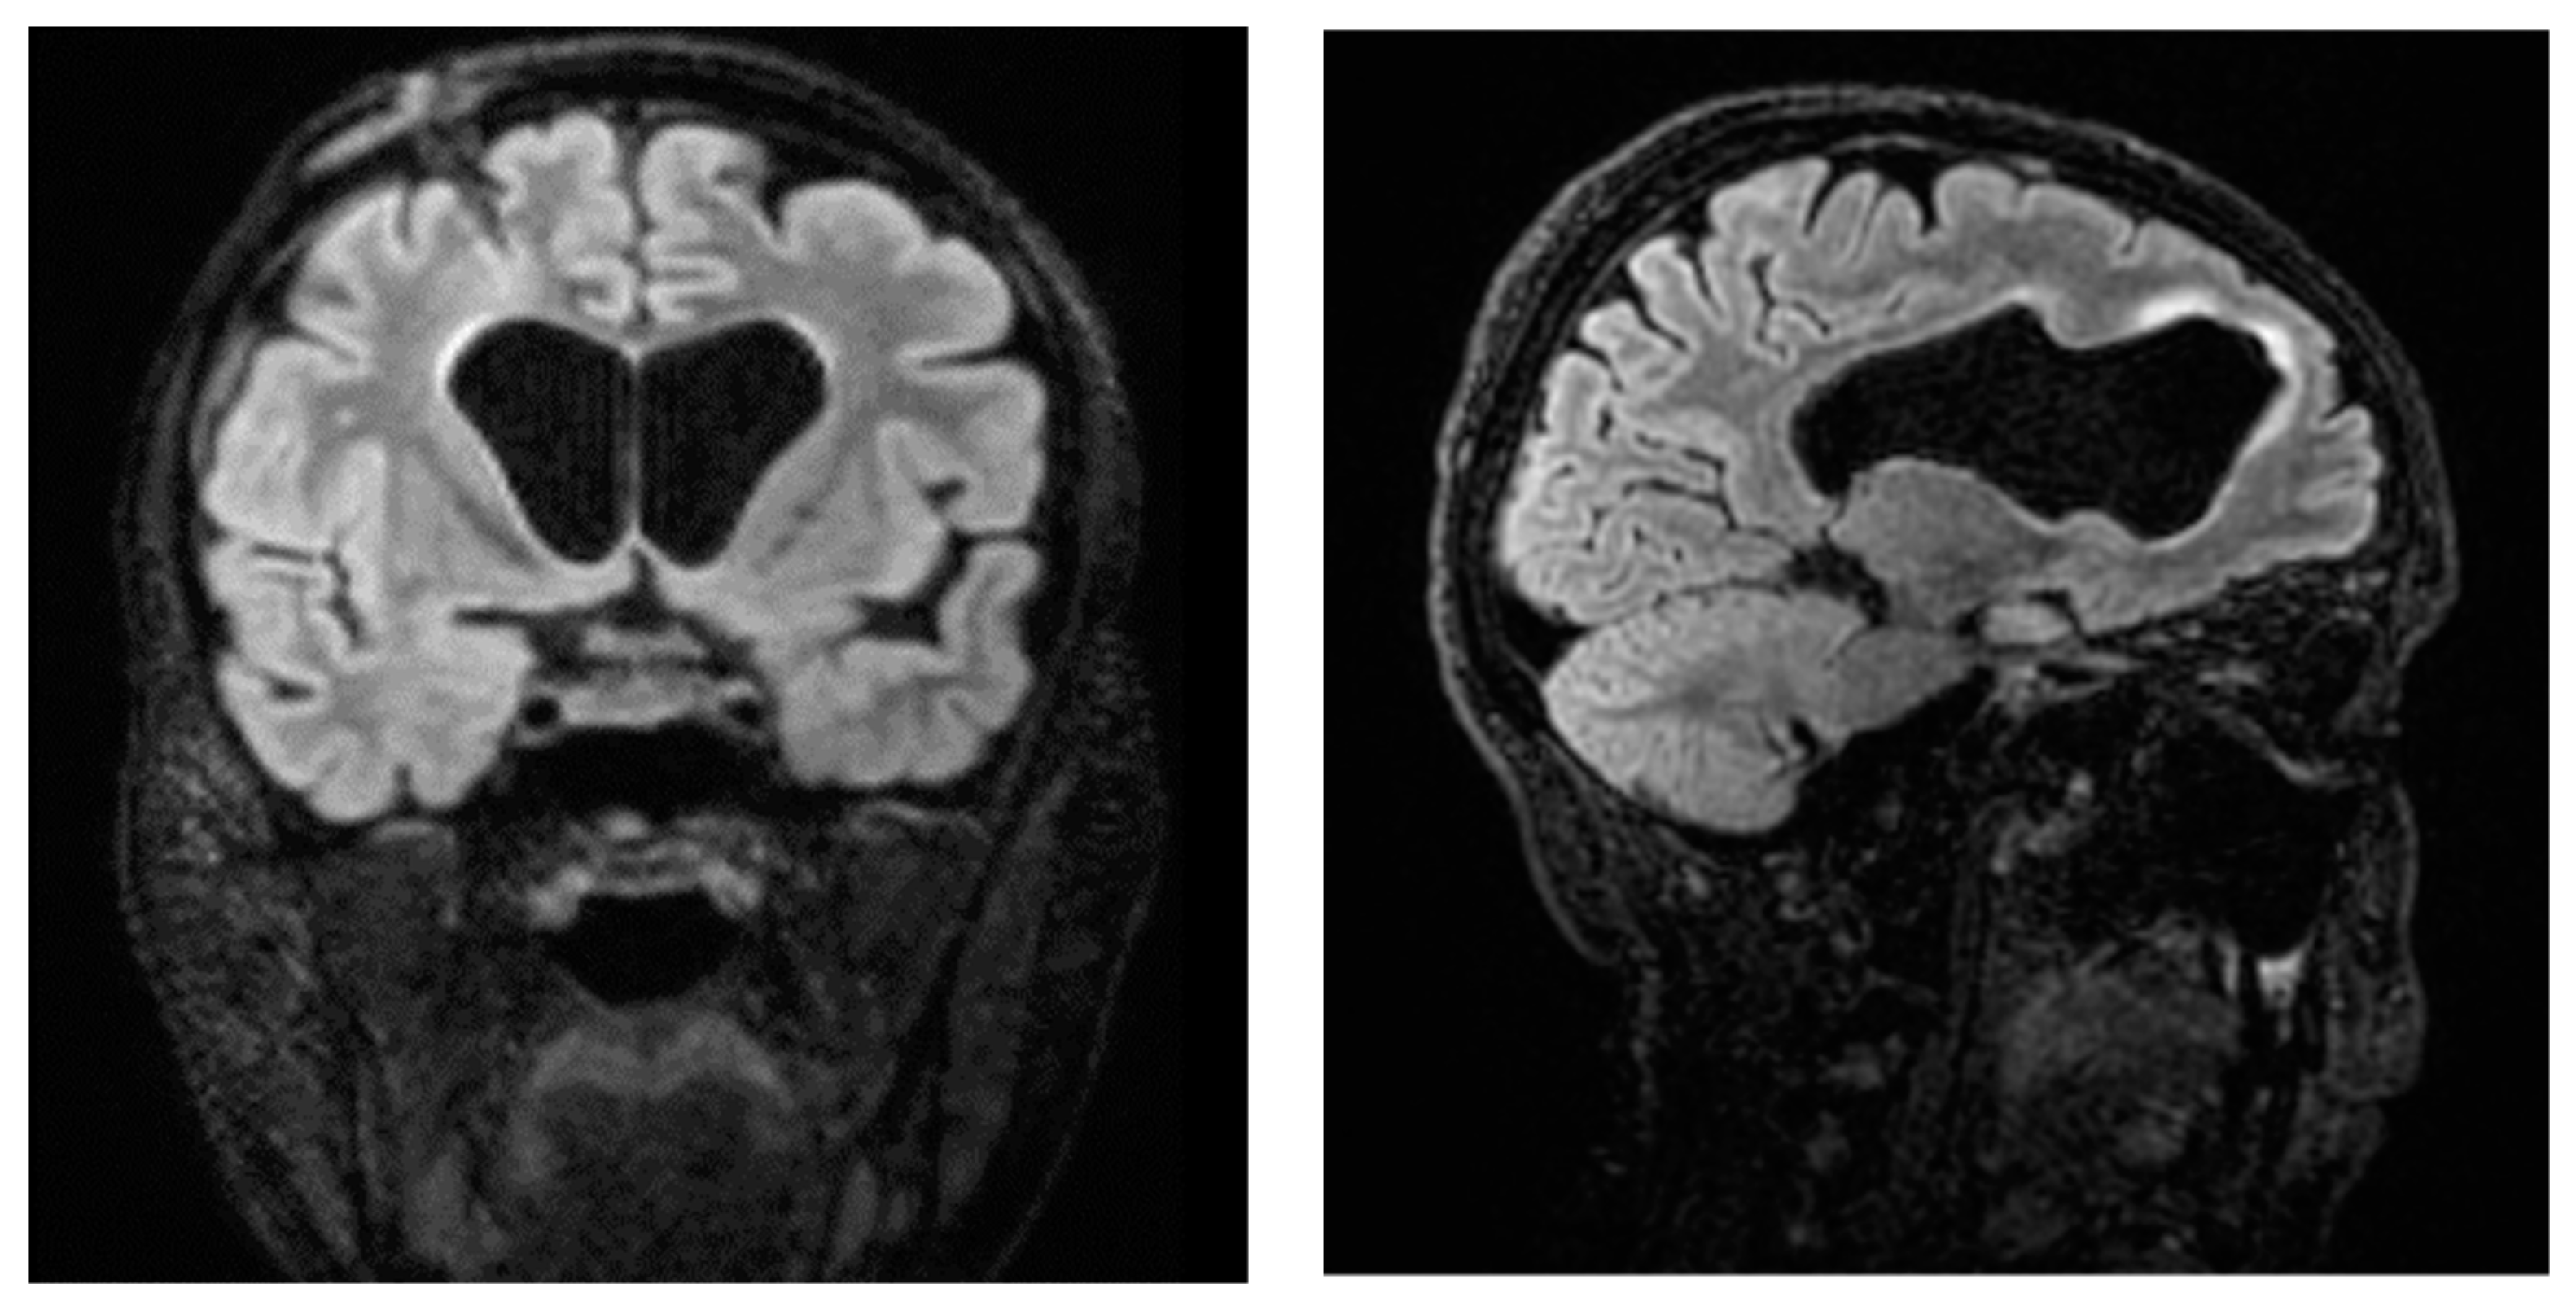

Ten days later, following a recurrence of fever and abdominal pain symptoms, as well as a sudden deterioration of neurological objectivity, the patient underwent another CT scan of the abdomen with contrast medium, which revealed the presence of an extensive collection (anteroposterior diameter 13.7 cm x transverse diameter 7.4 cm x lateral diameter 10.8 cm) at the distal extremity of the ventriculoperitoneal shunt. At the source control, KPC K. pneumoniae was found in the drained collection and in the CSF. Contrast-enhanced brain resonance imaging revealed a picture of tetraventricular hydrocephalus and periventricular hyperintensity in the fluid-attenuated inversion recovery (FLAIR), which was attributed to transependymal exudation phenomena, as well as the flattening of the adjacent periencephalic sulci, indicating ventriculitis [Figure 1]. Again, meropenem/vaborbactam therapy was started and continued for 21 days, and after multidisciplinary evaluation, the placement of ventriculoatrial derivation with the Codman Hakim system (calibrated to 110 mmH2O) was decided upon. Afterwards, no further infectious episodes were recorded. Figure 2 displays a timeline describing the clinical history. The patient experienced failure of the first-line therapy for acute leukemia, and a second-line therapy with azacitidine and venetoclax was started. In November 2023, she successfully received an allogeneic bone marrow transplant. The patient is doing well and is being followed up at our hospital’s Hematology Unit.

Figure 1.

Contrast-enhanced brain resonance imaging revealing a picture of ventriculitis.